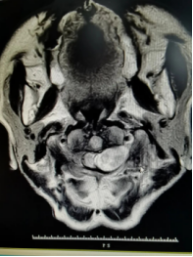

术前 术后

术前术后的影像图片对照

本次手术病人的肿瘤位于颅颈交界处,手术风险相对较高,稍有不慎就可能导致脊髓和血管的损伤,引起严重后果。患者赖婆婆已经出现严重的神经压迫症状,手术是唯一办法。术前通过充分评估,患者虽然已82岁高龄,但身体机能还比较好,手术成功率高。在市人医神经外科、麻醉科、影像科等多学科配合的前提下,最大限度保证了患者的医疗安全。为赖婆婆实施的“颈椎管肿瘤切除术”,整个过程只用了一个多小时,术中严格控制出血和减少创伤,全切肿瘤,且神经血管保护良好,手术过程顺利,术后患者情况稳定,神经症状明显缓解,术后一周康复出院。